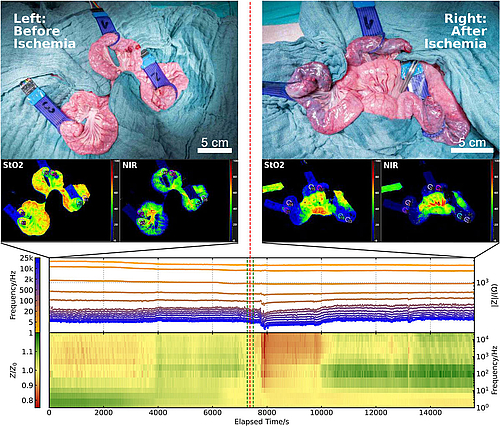

Das Sensorsystem basiert auf der getesteten PDO-Membran mit siebgedruckten Metallelektroden. Nach umfangreichen Material- und Stabilitätsuntersuchungen wurde die Sensormembran erfolgreich im Schweinemodell getestet. Dabei konnten kontinuierliche Bioimpedanzmessungen im Bereich der Anastomose durchgeführt werden. Nach experimentell induzierter Ischämie zeigten die Messungen reproduzierbare charakteristische Impedanzveränderungen, die bereits wenige Minuten nach Gefäßverschluss auftraten. Die Ergebnisse wurden zusätzlich mit einem hochpräzisen Labormesssystem bestätigt.